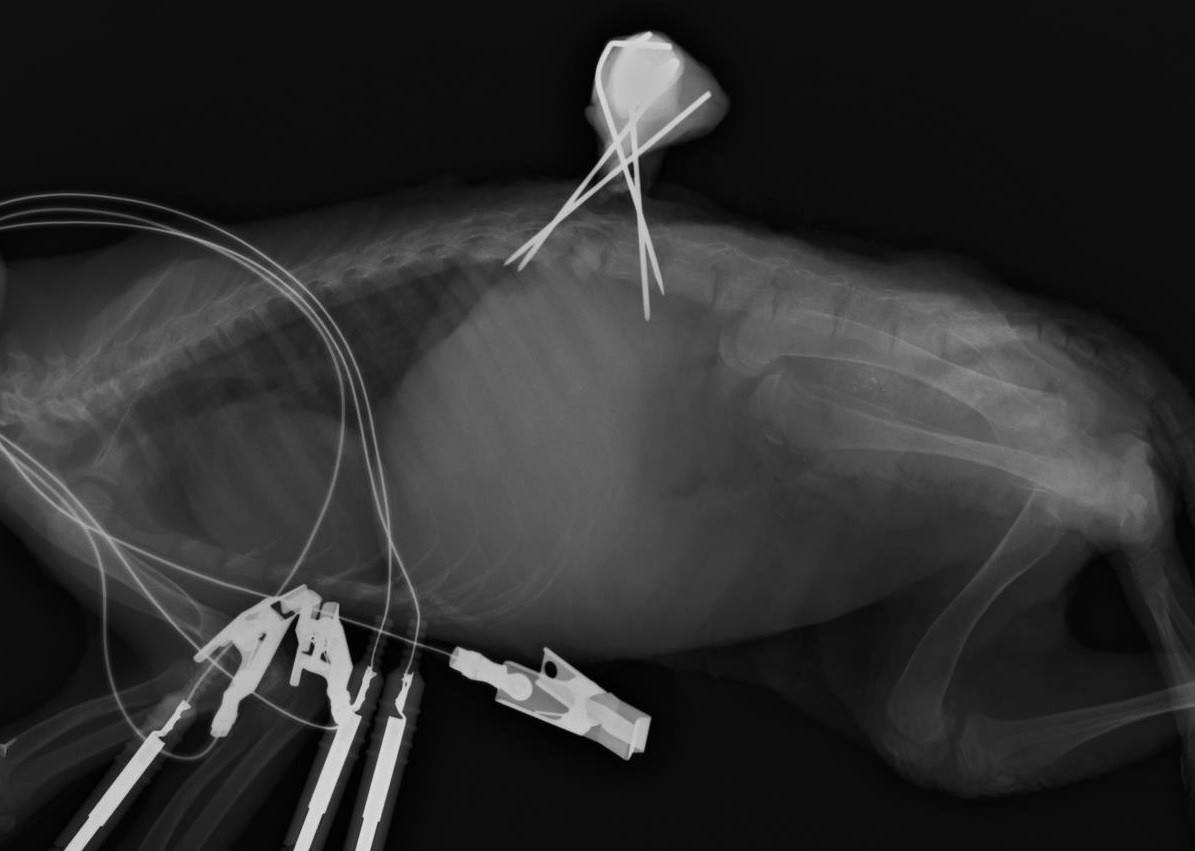

やはり、脊椎に異常が。腰椎を骨折しておりました。個体の状態はあまりよくありませんが、急を要するため、すぐに手術を行う事になりました。骨折部の骨を少し削り、脊髄が圧迫されない様な処置を行ったうえで医療用のピンを使って固定することにしました。

術後しばらくは起立できない状態が続いていましたが、いまでは他のタヌキとの違いが分からないぐらい元気に動き回っています。